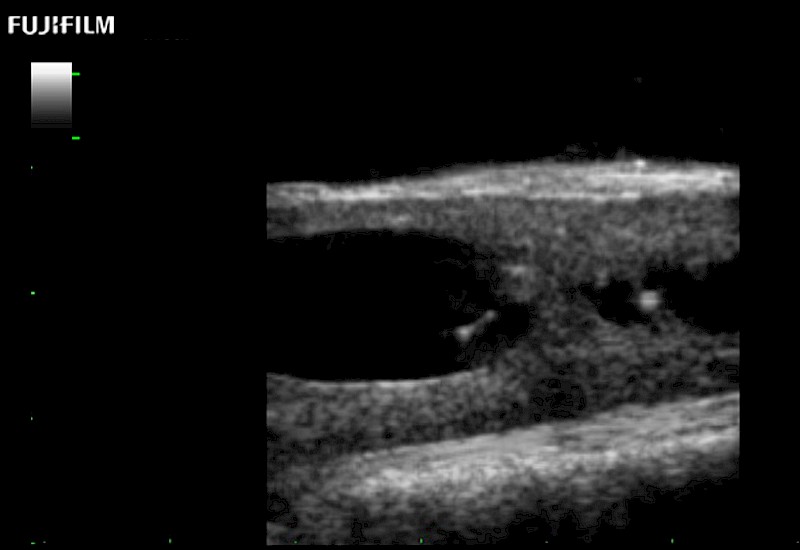

Exclusive 10mm side‐fire linear array transducer with 2.87mm diameter is ideal for real‐time visualization through and behind structures and instant, scalable definition of anatomy and vascularity including the ability to delineate and define tumor margins.

Main Specifications:

Hockey-stick linear array transducer is the transducer of choice for cervical spine scanning.